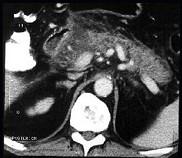

问题 男,32岁,上腹部持续性疼痛,放射至胸背部,高热,恶心呕吐,上腹部压痛反跳痛,CT检查如图,最佳的诊断是 ( )

选项 A.急性单纯性胰腺炎 B.出血坏死性胰腺炎 C.慢性胰腺炎 D.慢性胰腺炎急性发作 E.胰腺癌

答案 B